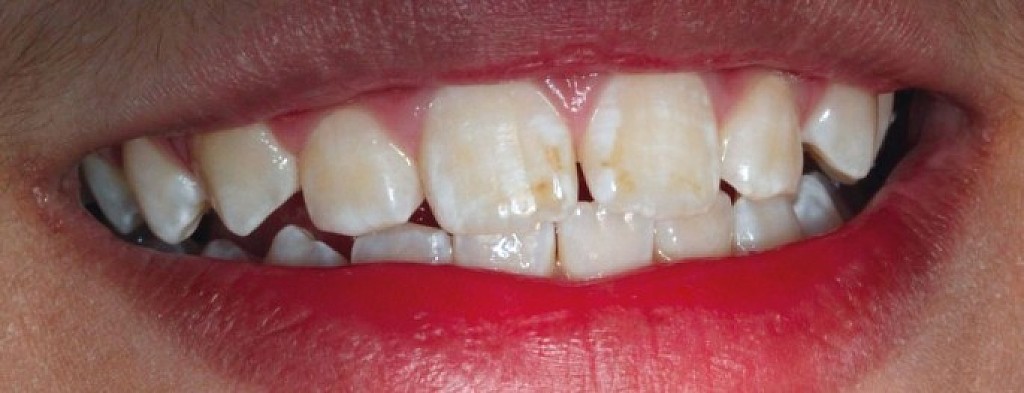

Enamel is the hard, protective outer layer of your teeth. Enamel hypoplasia is a defect of the enamel that only occurs while teeth are still developing. Still, it can affect both baby teeth and permanent teeth. The condition results in thin enamel, which makes your teeth vulnerable to dental decay.

The visual signs of enamel hypoplasia include white spots, pits, and grooves on the outer surface of the teeth.

Some of the signs of enamel hypoplasia are obvious, but others are more difficult to detect and may not be noticeable until they cause major dental problems. Having thin tooth enamel can lead to:

pits, tiny groves, depressions, and fissures

white spots

yellowish-brown stains (where the underlying layer of dentin is exposed)